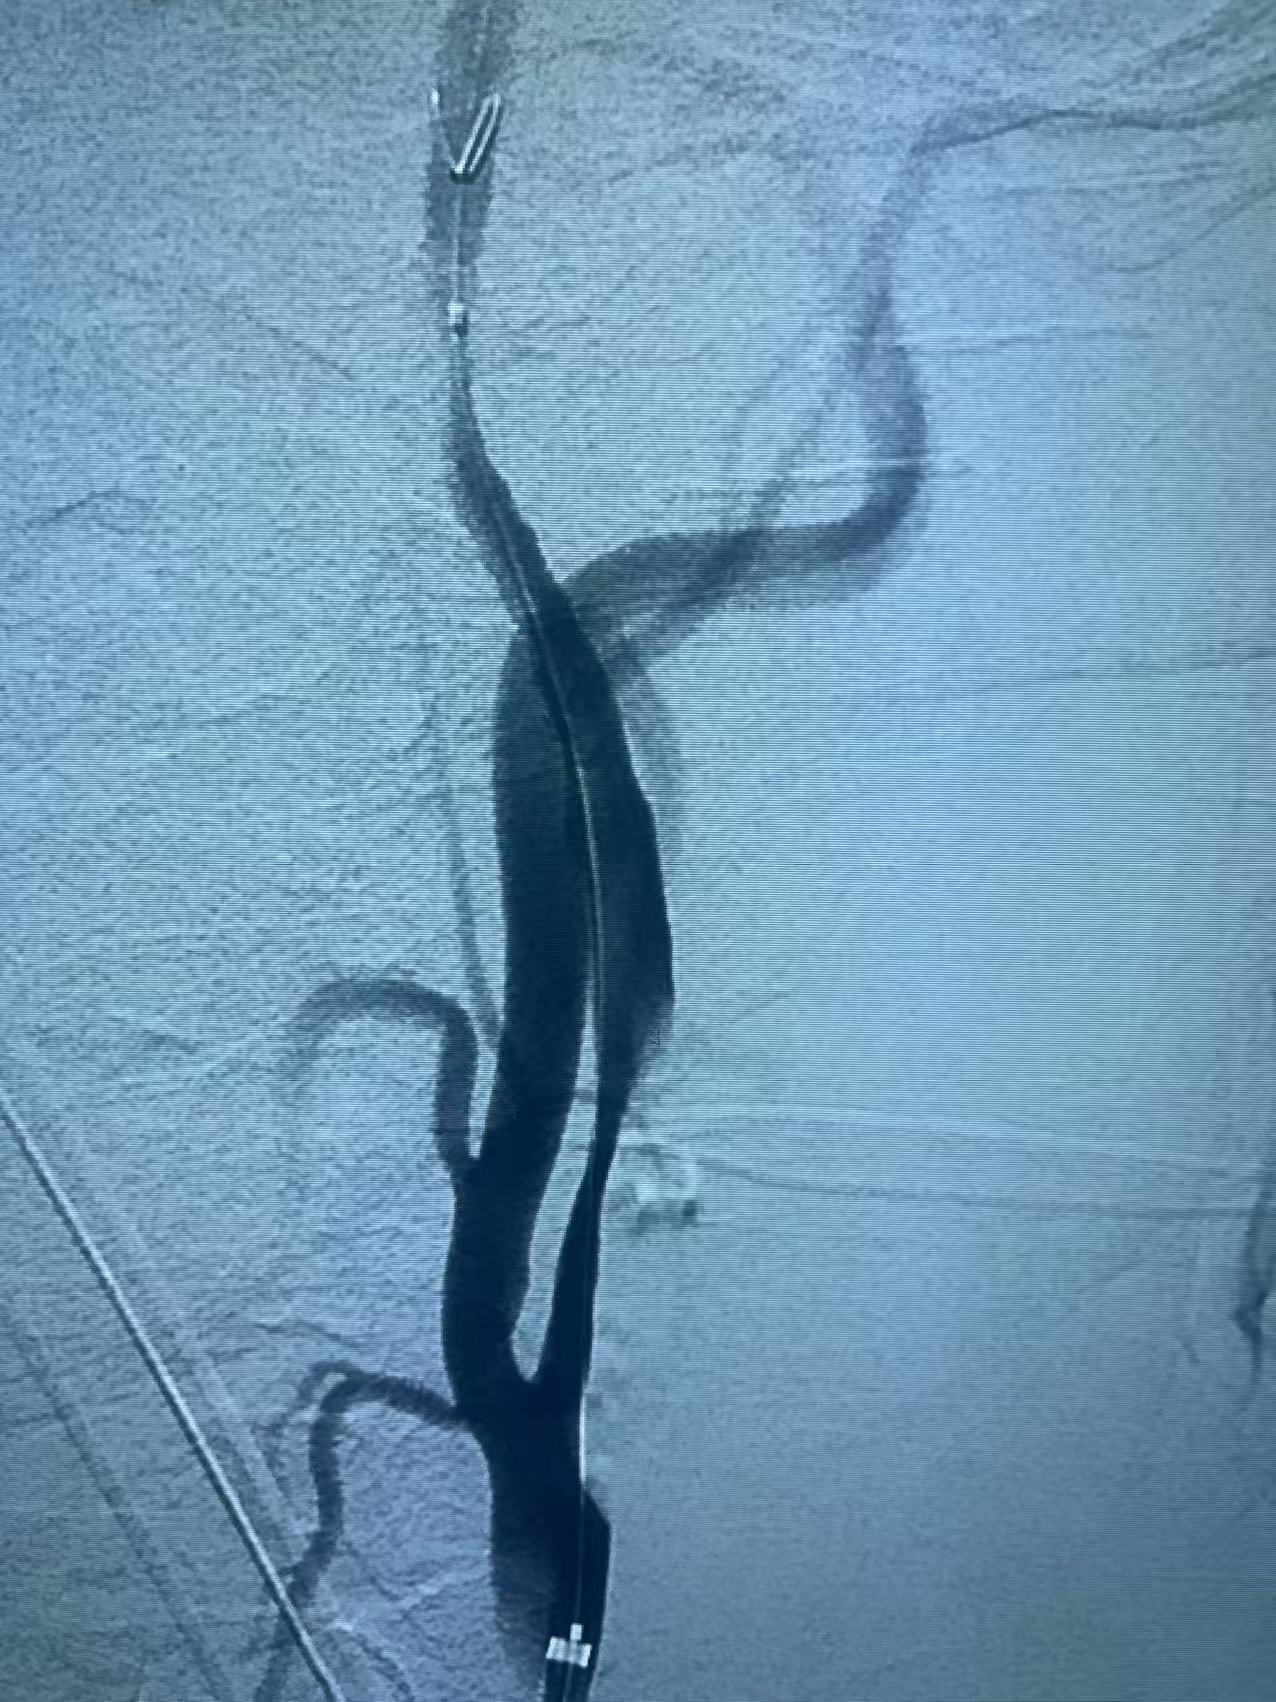

颈内动脉开口重度狭窄基础之上的急性闭塞